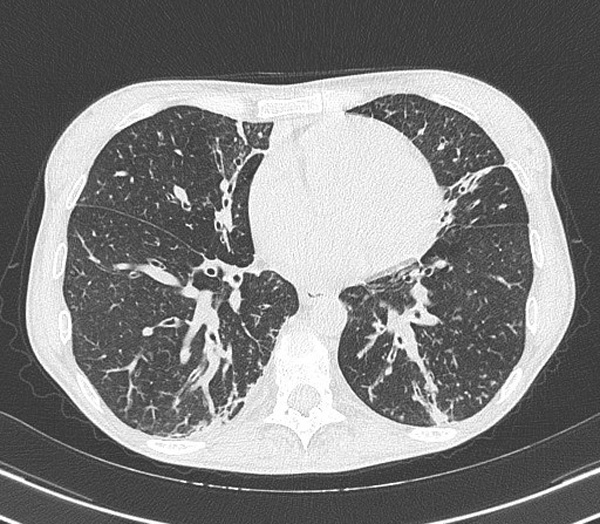

Chest X-ray (Figure 1) and chest CT (Figure 2), compared with the previous tests available, showed an unchanged picture of bilateral bronchiolitis characterized by millimetric center-lobular nodulations partly confluent and by thickening areas located in the medial segment of the middle lobe, in the lingula and in the postero-basal regions of both lower lobes, with greater extension to the left. Instead, a small, faint left retrocardiac thickening had appeared. Therefore, at ward admission, the patient was diagnosed with lower respiratory tract infection, with partial respiratory failure, in a CVID picture.

Figure 2. Chest CT performed in August 2021.